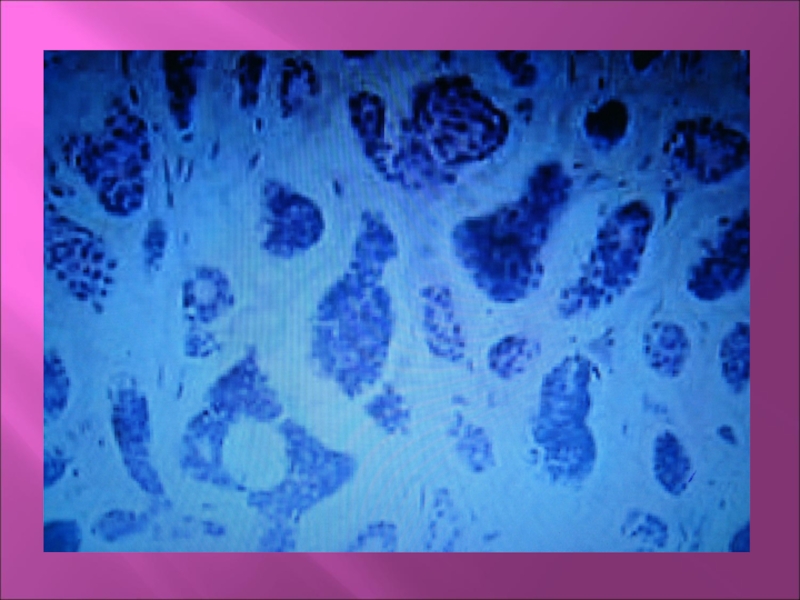

Слайд 45Цистаденоидная карцинома (цилиндрома)

Чаще поражает малые железы.

Макроскопически: узловая и диффузная

формы.

Микроскопически: мономорфные мелкие клетки, между ними накапливается секрет, что приводит

к образованию просветов.